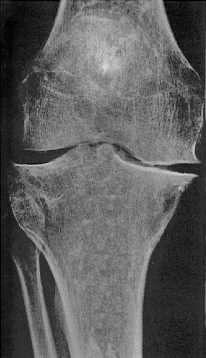

Röntgenbild eines nicht mehr ganz taufrischen Kniegelenkes

Ganz ohne Röntgen kann kein Orthopäde arbeiten. Die Gefährlichkeit von Röntgenstrahlen wird oft weit überschätzt, trotzdem: gesundheitsfördernd sind sie nicht!